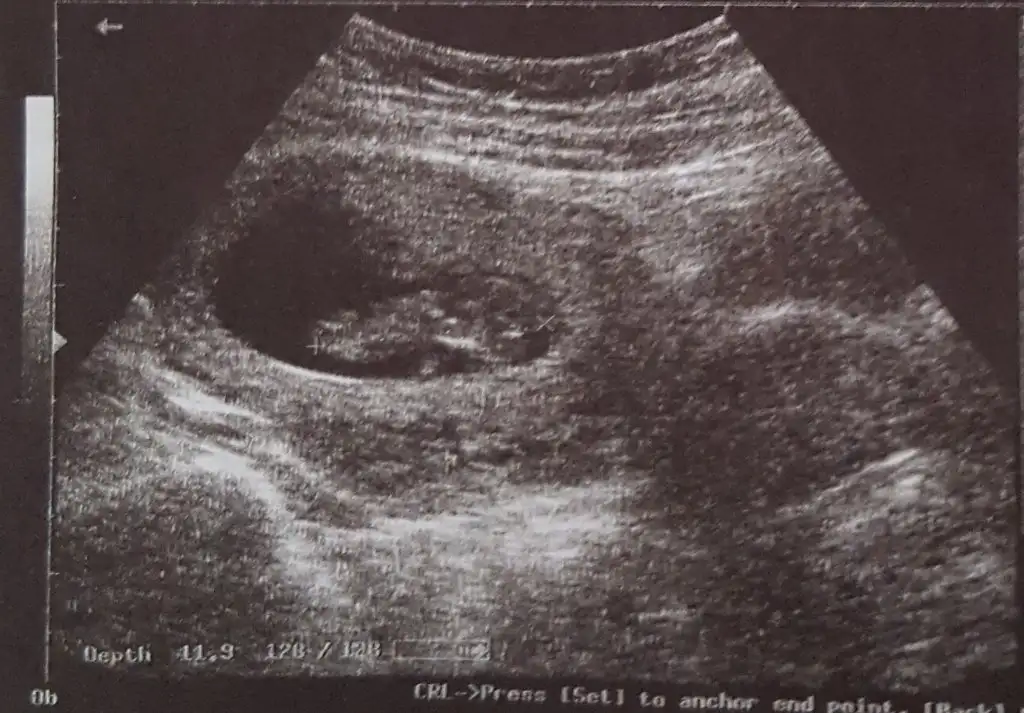

Bi bakabilir misiniz 12+6 oldukdr göremedim dedi.yorumlayabilirmisiniz

Atın bakim ama en iyi 11 12 13 haftalar10+3 atsam bakabilir misiniz

12 de tekrar gidicem o zamanda atarım merakıma yenildimAtın bakim ama en iyi 11 12 13 haftalar![]()